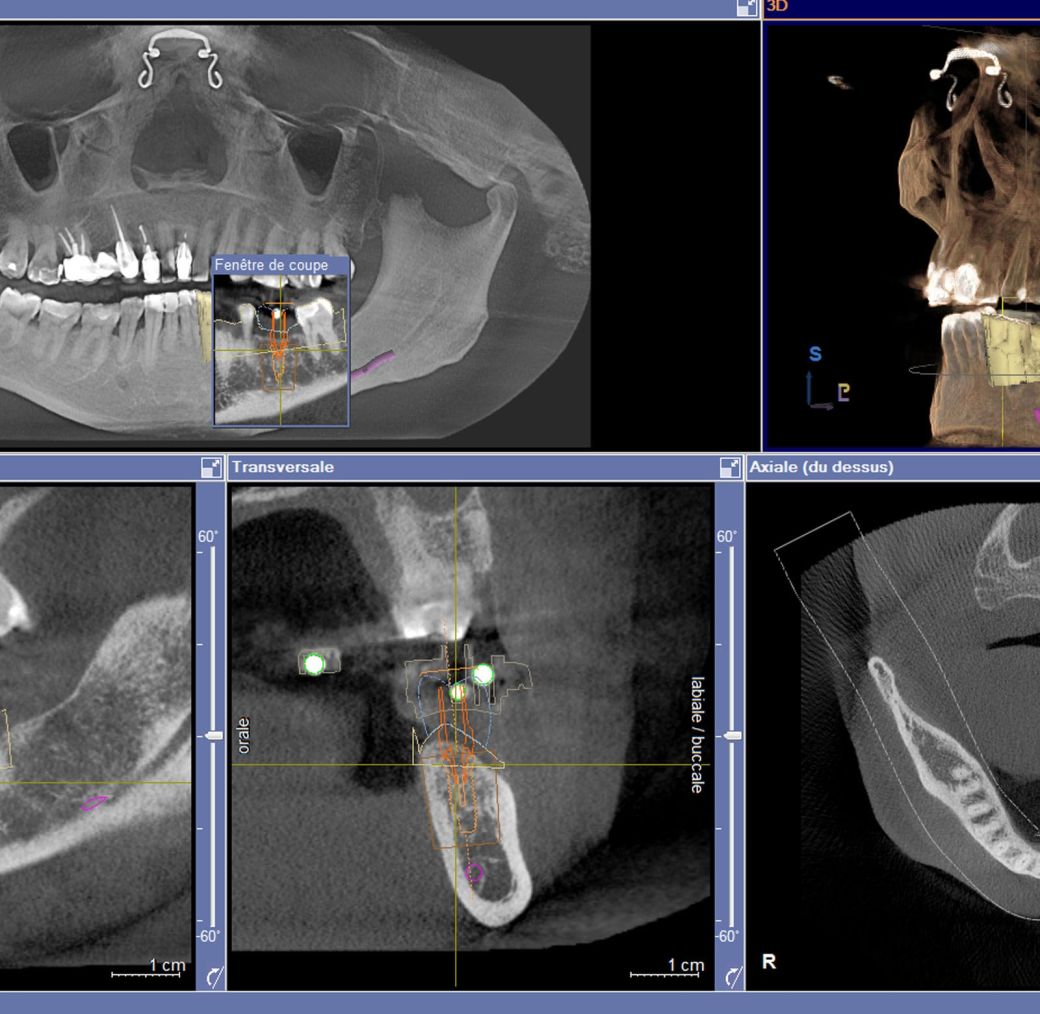

Le Cône Beam (CBCT)

C’est l’examen de choix pour la réalisation de la planification implantaire.

La planification implantaire

La planification implantaire consiste à déterminer le choix du nombre, de la longueur, du diamètre et de la position des implants, ainsi que leur orientation dans les différents plans de l’espace.

Dans ce cas clinique, la planification implantaire tient compte, pour la pose d’un implant localisé sur le site 36, du projet prothétique final (ici une couronne matérialisée en bleu).

Le nerf dentaire inférieur, élément noble à respecter dans cette chirurgie implantaire, est ici schématisé en violet.